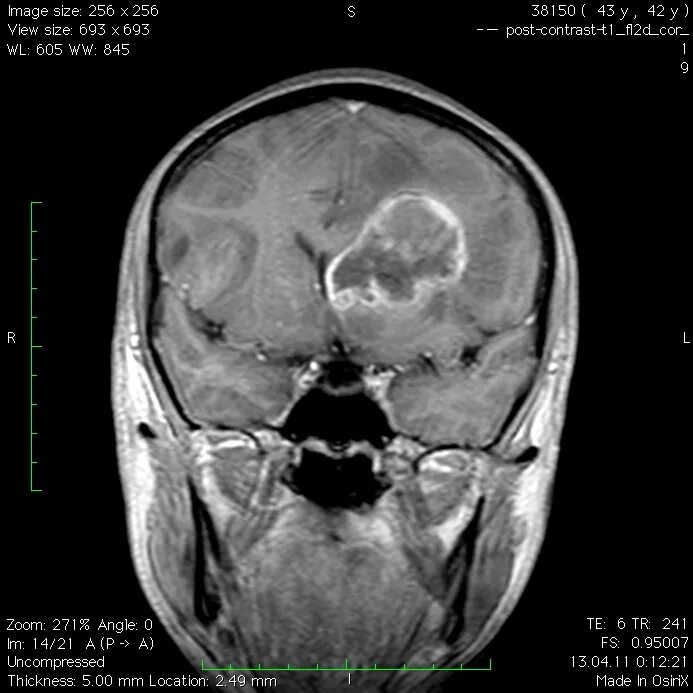

Мрт симптомы